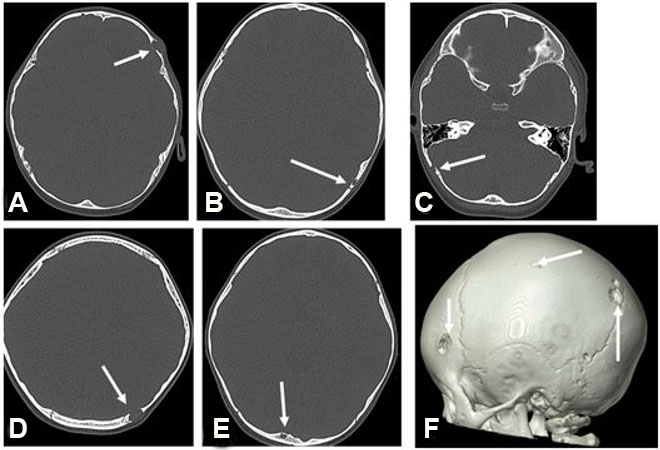

A previously healthy 2-year-old male presented with pneumonia. His workup revealed a bump on the left side of his head. He had no associated constitutional symptoms such as weight loss, fever, headaches, or seizures. He underwent imaging, including head and chest computed tomography (CT) and head magnetic resonance imaging (MRI). The latter revealed multiple ring-enhancing intra-axial lesions involving the gray-white matter junction of the bilateral frontal, left-sided parietal, left-sided occipital, and left-sided temporal lobes surrounded by significant vasogenic edema. The foci showed blooming artifact in the susceptibility weighted sequence (SWI) (Figure 1). The calvarium parietal bone showed the presence of multiple lytic intradiploic lesions associated with a soft tissue component (Figure 2). The skeletal survey did not reveal any lytic lesions. Abdominal ultrasound displayed an enlarged liver without focal lesions and no lymphadenopathy. The clinical considerations included inflammatory lesions, such as tuberculosis and fungal infection, and less likely multiple metastases. The patient is doing clinically well during follow-ups, and the MRI demonstrated improvements in intracranial lesions with no new parenchymal findings (Figure 1).

Figure 2: Axial CT in bone window. (A–E) demonstrate the presence of multiple lytic lesions (white arrows); (F) 3D reformat image shows multiple calvaria lesions.